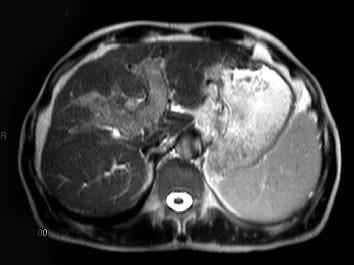

问题 男,65岁。右上腹部疼痛不适,乏力4月余。AFP升高。MRI如下图所示。应诊断为 ( )

选项 A、转移瘤 B、未见异常 C、胆管细胞癌 D、肝腺瘤 E、肝右叶肝细胞癌并门脉癌栓形成

答案 E